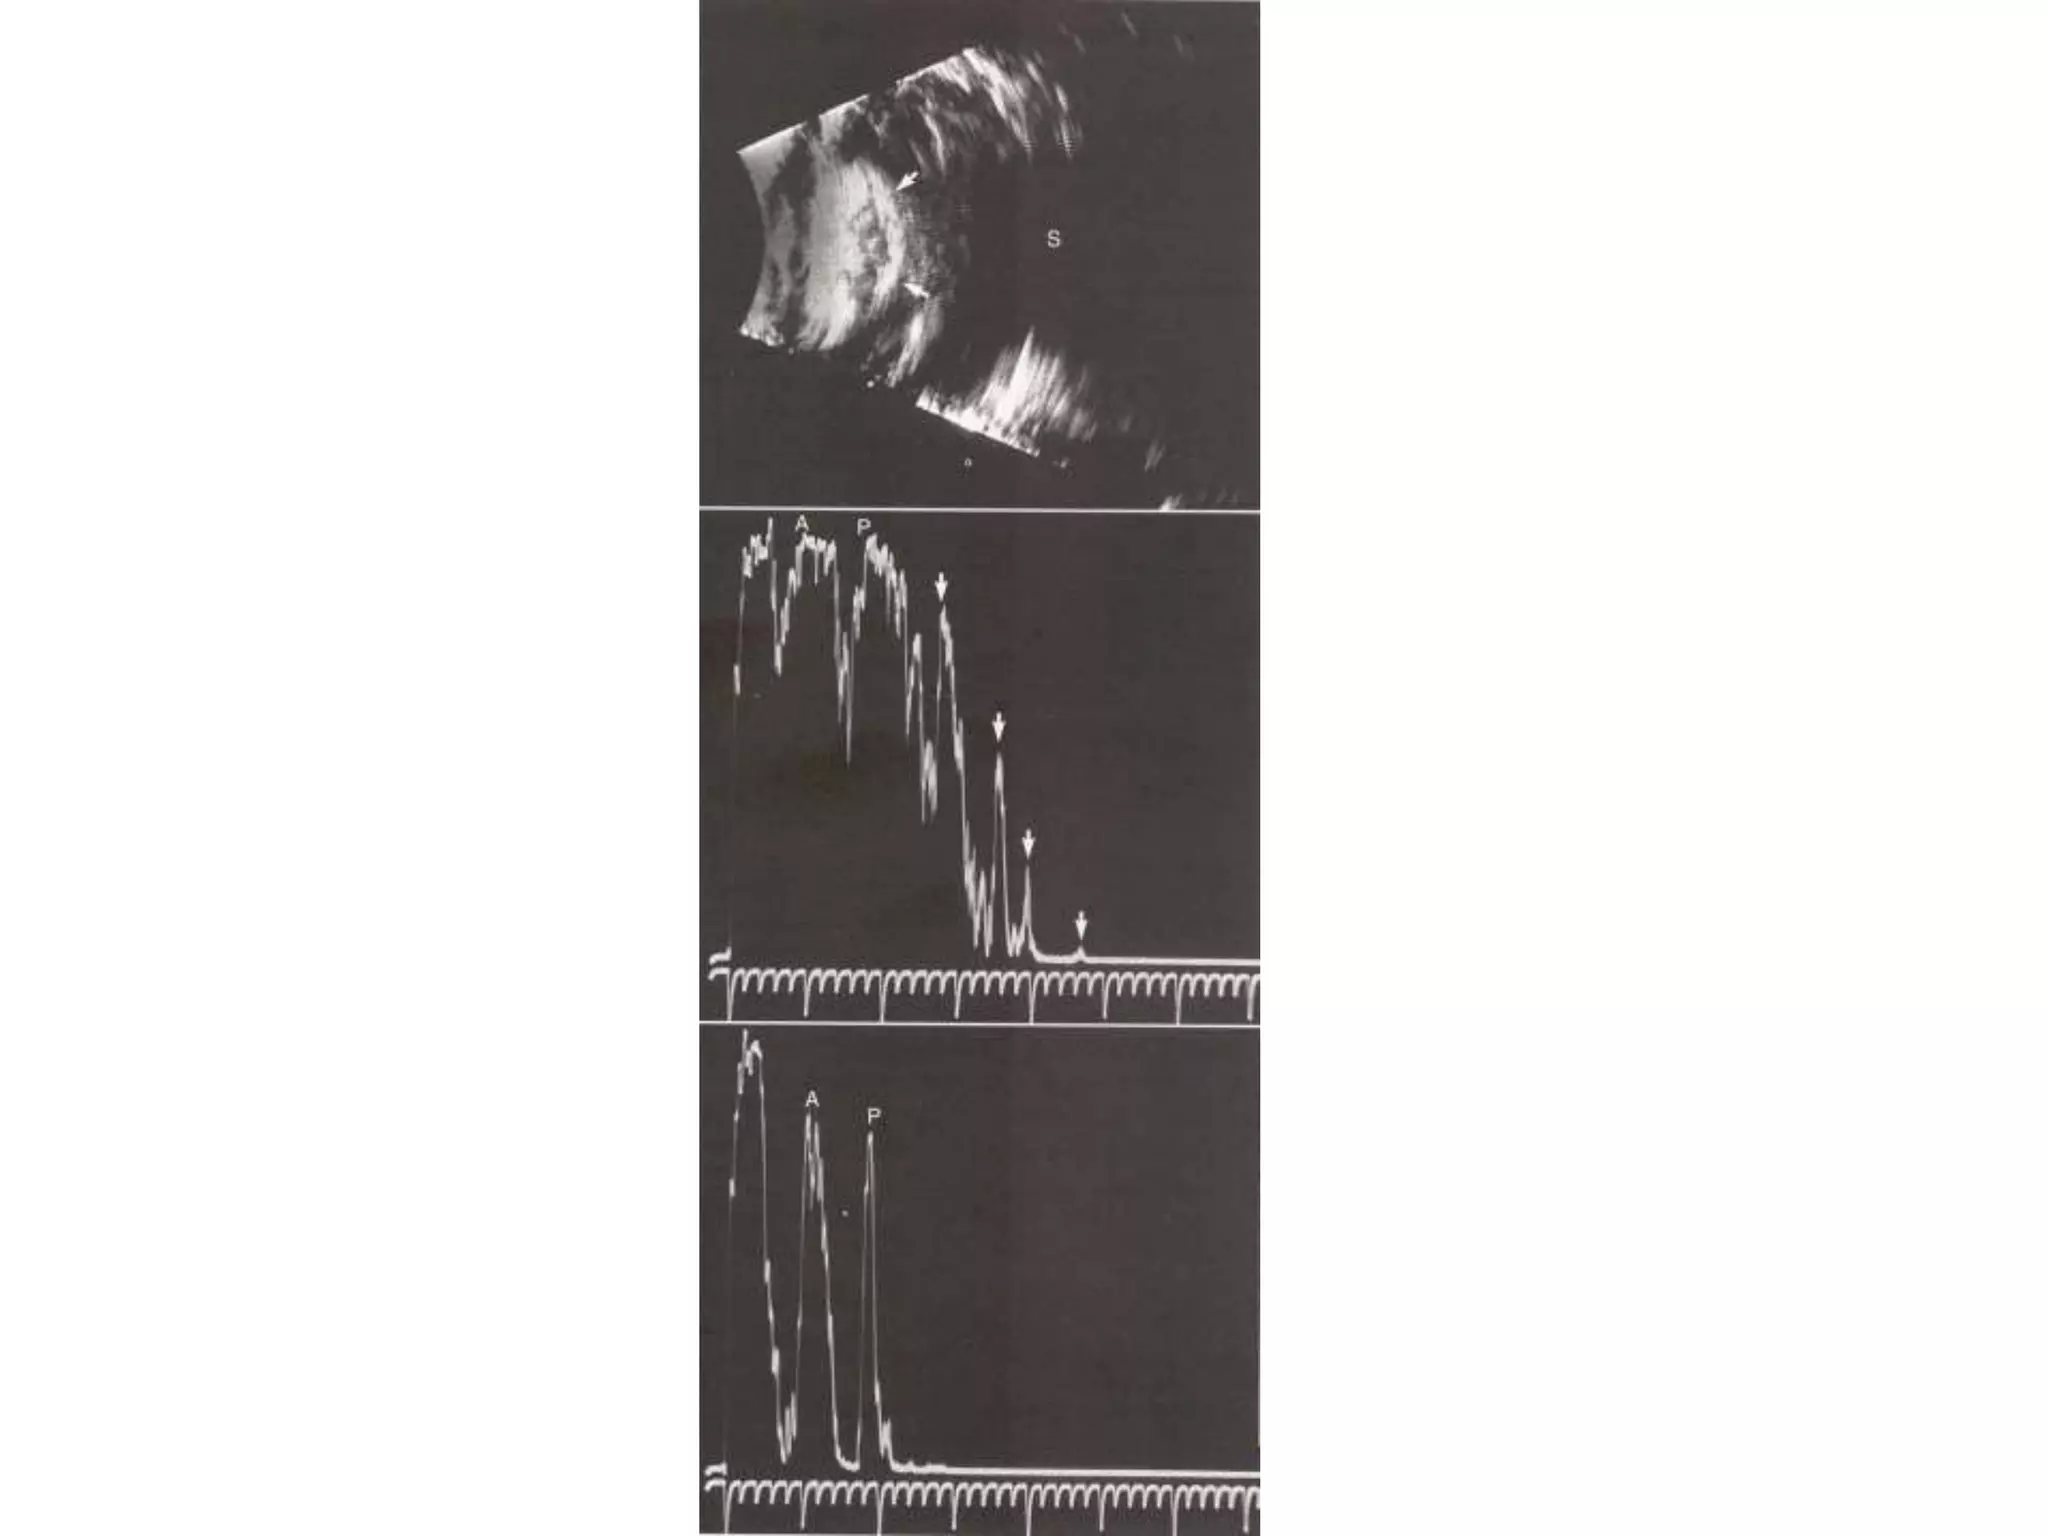

Vitreous Lesions

 Asteroid Hyalosis

 Vitreous Hemorrhage

 Gas Bubble

Macular Lesions

 RD

The presence of an elevated macular lesion may

prevent the display of a distinct retinal spike and

often causes a shortened AL measurement .